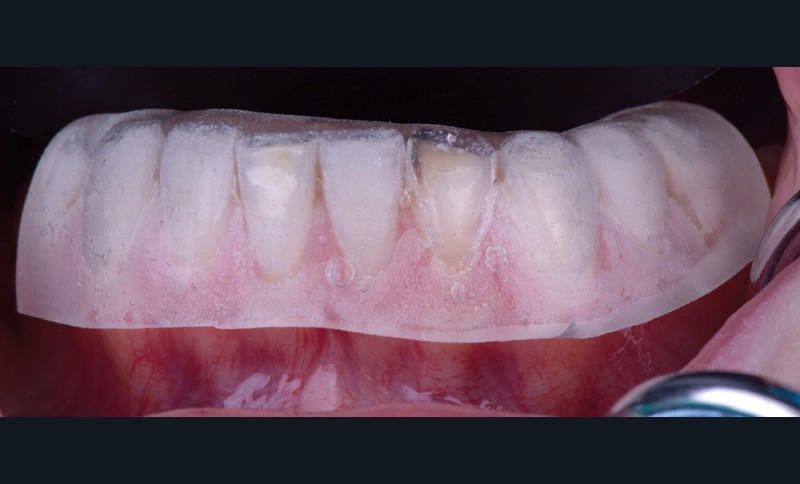

L’empreinte initiale doit être la plus précise possible. Elle doit enregistrer l’anatomie de la ou des dents concernées, mais aussi des dents adjacentes. En effet, la clé d’injection sera stabilisée sur les dents adjacentes. L’empreinte ne néces- site pas de préparation préalable des surfaces dentaires.

2. Wax up

Le wax-up est réalisé au laboratoire par le prothésiste (fig. 2). Il permettra de reproduire l’anatomie de la ou des dents concernées. Il est préférable de ne pas ajouter de cire dans la partie la plus cervicale de la dent afin d’éviter toute fusée de matériau composite lors de l’injection. Par ailleurs, la clé s’appuyant sur la partie gingivale, il est possible de gratter le plâtre d’un dixième de millimètre dans la zone du sulcus et sur la gencive. Cela permet de compenser la dépressibilité des tissus mous (fig. 3).